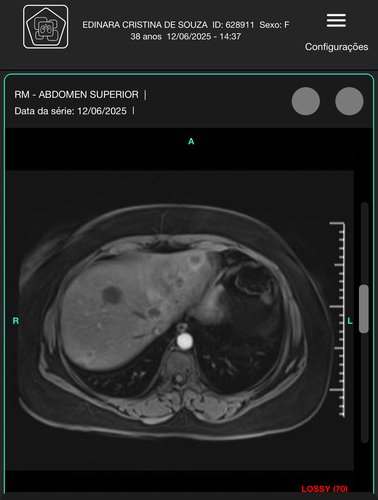

Eu sou Nara,em abril descobri um câncer de mama com metástase no fígado.Faço quimioterapia a cada 21 dias.Trabalhava de costureira,mas de lá pra cá não consigo ficar muito tempo na máquina,faço uns consertos pra ajudar,mas não é suficiente.E meu esposo voltou para nossa empresa de entregas pra poder me acompanhar no tratamento,mais ainda temos poucas entregas e as contas estão acumulando,já dei entrada no auxílio mas ainda não saiu autorização,então queria pedir ajuda de vocês para conseguir colocar tudo em ordem,para este novo recomeço.